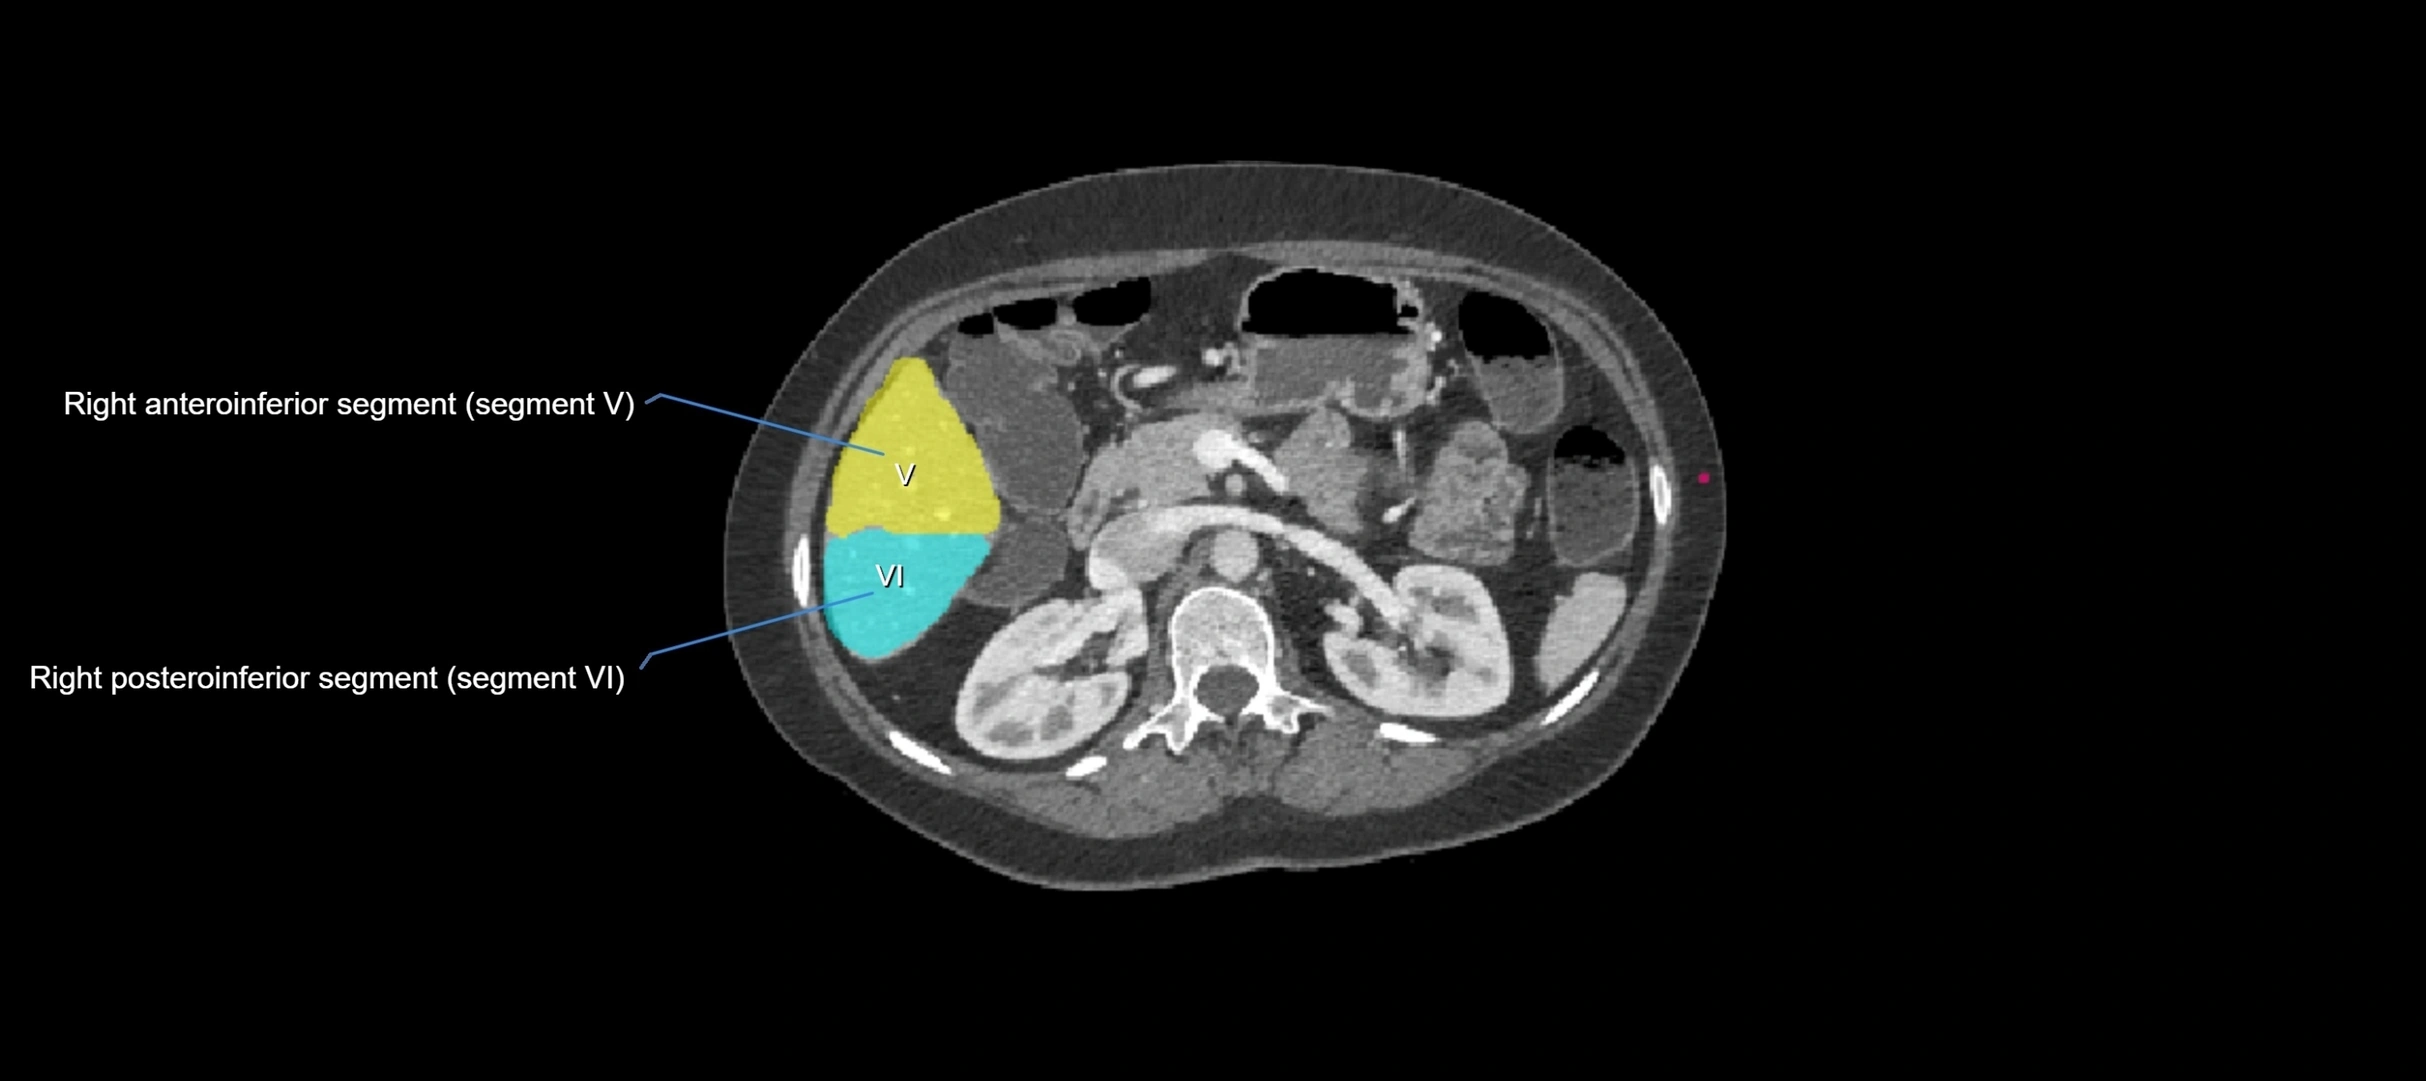

CT Image

image